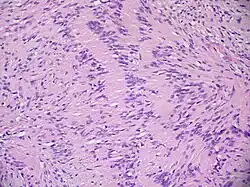

Невринома состоит из веретенообразных клеток с палочкоподобными ядрами. Клетки и волокна опухоли образуют «палисадные» структуры (ядерные палисады, тельца Верокаи) с участками, состоящими из волокон[29].

Традиционно различают два гистологических типа неврином: тип Верокаи, или тип А, и тип Антони, или тип Б. Данное разделение условно и практического значения для диагностики не имеет. Советский нейрохирург, академик АМН СССР Б. Г. Егоров при исследовании неврином слухового нерва обнаружил, что их структурное многообразие зависит не от изначальных свойств опухолевой ткани, а от деструктивных и рубцовых процессов[28].

Микроскопическое строение опухоли на разных стадиях роста может быть различным в зависимости от интенсивности дистрофических процессов и нарушений кровообращения. Нарушения кровообращения сопровождаются скоплением гемосидерина и разрастанием фиброзной ткани. Всё это создаёт пёструю гистологическую картину[28].

Количество сосудов в ткани опухоли значительно колеблется. Периферические отделы обычно окружены богатой сосудистой сетью: в центральных участках их количество варьирует от одиночных, до сосудистых клубков, напоминающих по строению кавернозную ангиому. Стенки сосудов тонкие, иногда образованы одним слоем эндотелия, но могут встречаться сосуды с резко утолщёнными гиалинизированными стенками[28].